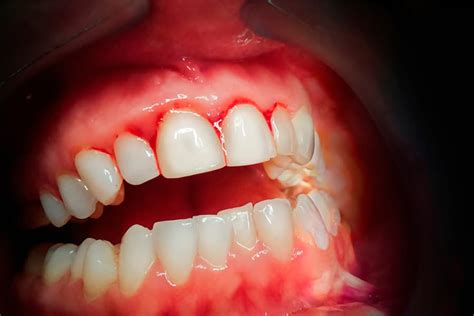

El sangrado de encías es un problema común que puede indicar una variedad de problemas subyacentes, desde una higiene bucal deficiente hasta condiciones de salud más serias. Es crucial identificar las causas y buscar el tratamiento adecuado para mantener una buena salud bucal y prevenir complicaciones a largo plazo.

- Gingivitis: Es la causa más común del sangrado de encías. Se trata de una inflamación de las encías, generalmente causada por la acumulación de placa bacteriana debido a una higiene bucal deficiente.

- Periodontitis: Si la gingivitis no se trata, puede progresar a periodontitis, una infección más grave que daña los tejidos blandos y el hueso que sostienen los dientes.